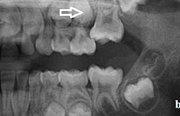

Esimeste molaaride (purihammaste) lõikumine. 1. molaaride ektoopilise lõikumise jälgimine. Ülemised ja alumised esimesed purihambad e. molaarid lõikuvad orienteeruvalt6-7-aastaselt piimahammaste rea lõppu. Enamasti lõikuvad samanimelised jäävhambad paaridena. Normaalne lõikumise Loe edasi »

- valehambumus (18)